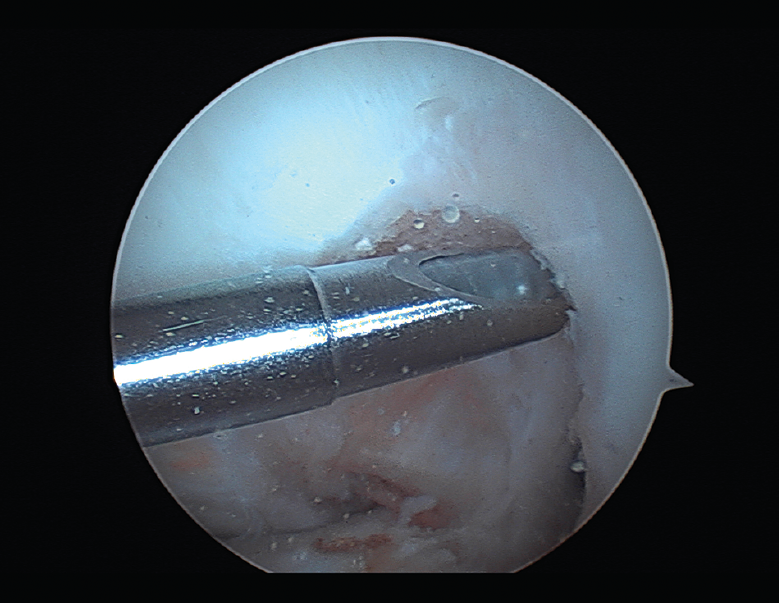

Las principales causas secundarias a errores técnicos son la malposición de la plastia y el tensado excesivo. La radiografía permite ver la localización de los túneles e implantes, así como la RM visualiza las partes blandas implicadas, pudiendo identificar posibles pinzamientos de la plastia –escotadura intercondílea, síndrome del cíclope (Figura 9), síndrome de la contractura infrapatelar(22)(Figura 10)–.

Figura 9. Cíclope, tejido fibroso interpuesto en la cara anterior de la plastia y que produce pinzamiento de la misma en extensión de rodilla.